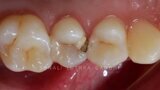

Management of proximal posterior lesions- A case report